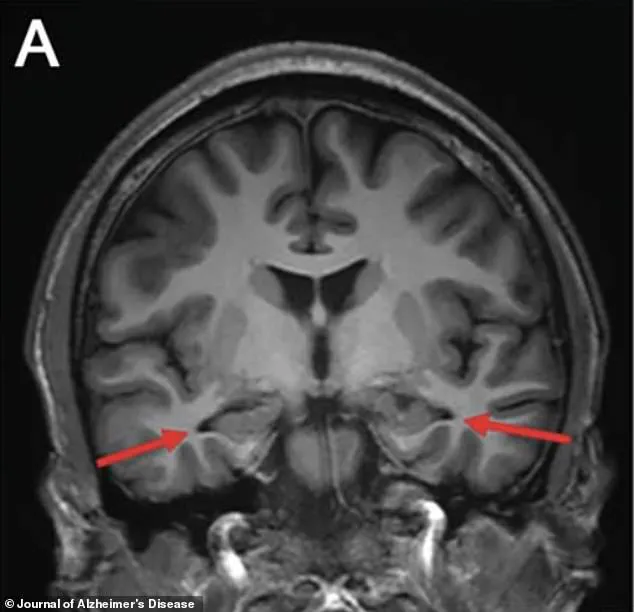

Brain scans conducted in 2022 provided further evidence of the disease's presence.

These scans revealed significant shrinkage in the hippocampus, a critical region of the brain responsible for memory formation.

The hippocampus is one of the first areas affected by Alzheimer's, and its deterioration is a hallmark of the disease.

An MRI revealed a critical anomaly: the hippocampus, the brain's primary memory center, was visibly shrinking.

Additional scans confirmed reduced activity in the parietal and temporal cortices, regions crucial for memory and critical thinking.

These findings were further highlighted by arrows on the MRI images, drawing attention to the atrophied areas.